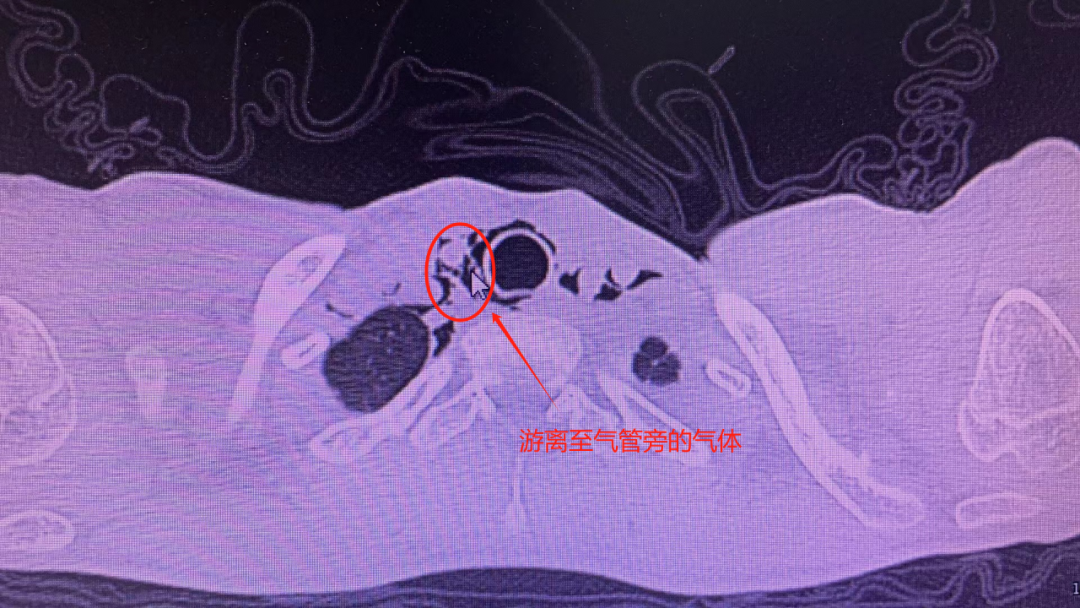

据东东妈妈表示,东东咳嗽一直很严重,入院当天甚至还出现了胸痛、精神萎靡不振的症状,急得家长赶紧将孩子送往浙大四院。经急诊医生迅速判断,东东这是因反复剧烈咳嗽导致的纵膈气肿,也就是俗话说的把肺咳「破」了。

「从肺里破出来的气体进入到纵膈的间隙里面,形成纵膈气肿,导致孩子胸痛,脖子有紧绷感,吃东西、咽口水也痛得厉害。」浙大四院心胸外科俞江灏医生表示。

纵膈气肿是指空气从肺部、气管或食道渗漏进入纵膈胸膜内结缔组织间隙之间,导致纵膈腔内出现游离空气。其症状与纵膈气肿发生的速度、积气量等相关。常见的症状为胸痛、呼吸困难和颈部的皮下气肿,医学上称之为「纵膈气肿三联征」。